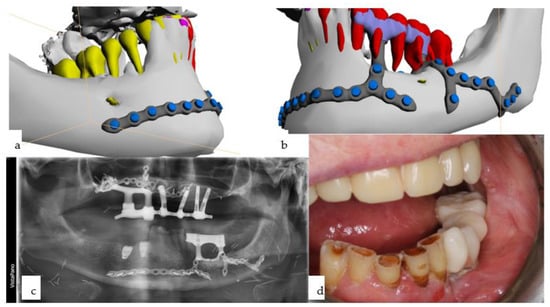

Figure 11. (ag): Primary onset of squamous cell carcinoma of the maxilla began in 2012 following prolonged treatment with tacrolimus ointment administered by dermatologists (a,b), necessitating subtotal maxillectomy (c) with soft tissue reconstruction to separate the bilateral nasal and paranasal regions from the oral cavity. Dental rehabilitation was carried out using a conventional dental implant treatment protocol with a telescoping suprastructure (d). In June 2018, a right maxillectomy was required due to tumor recurrence, and a two-stage subperiosteal IPS Implants® Preprosthetic procedure was performed (e), which was combined with bar-retained support along with the remaining 4 telescoping abutments on top of the dental implants (f). The prosthesis used was a removable overdenture designed to provide separation towards the vertical units of the cheeks and lips (g).